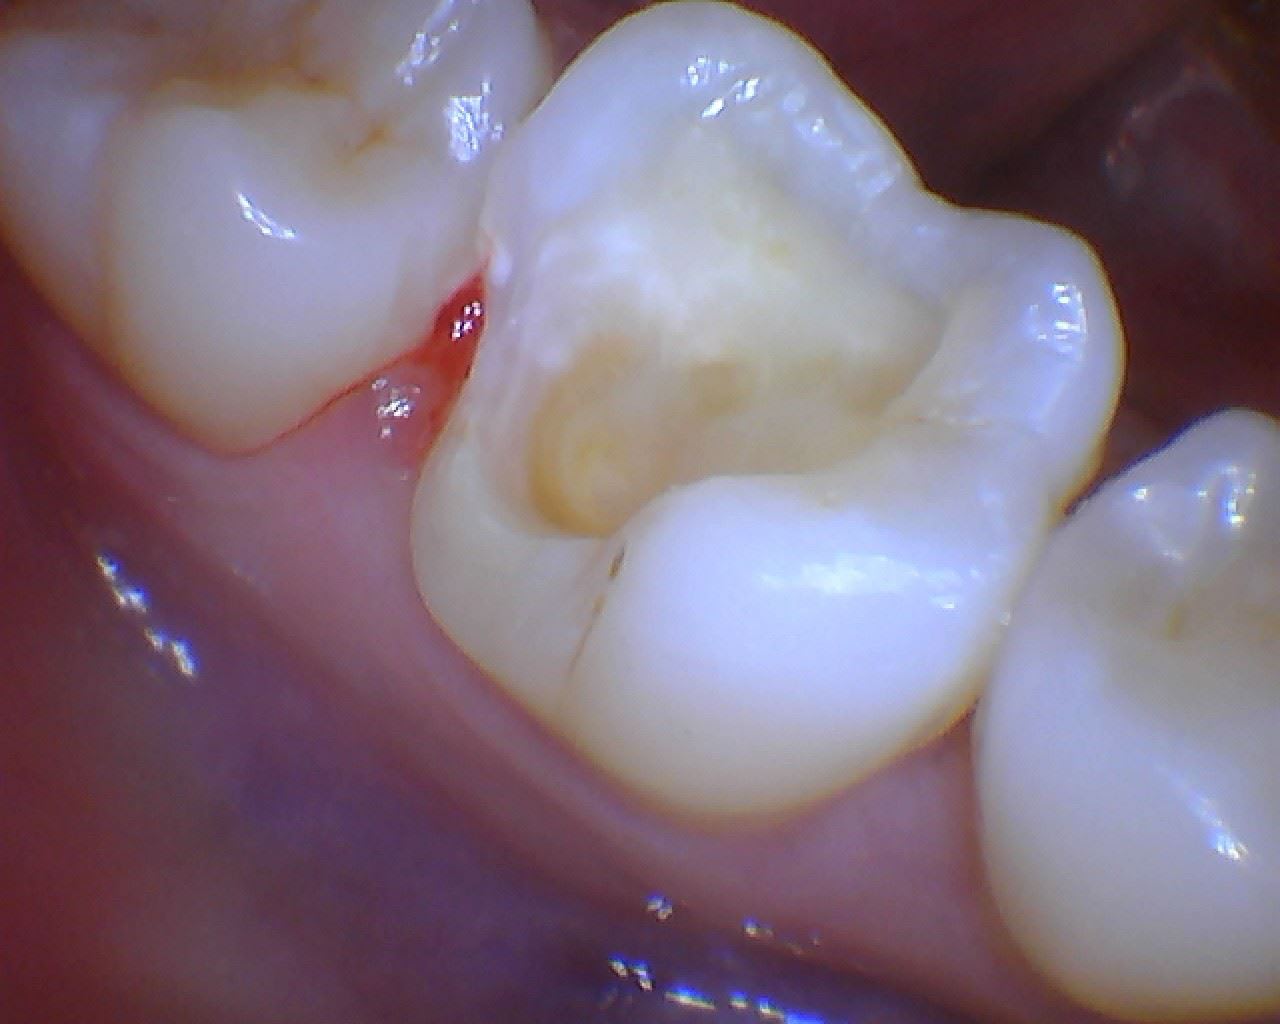

Patiente adorable 24 ans...

J'ai prévu un onlay, vous en pensez quoi.

J'ai pas créé de rétention type box ou queue (PP, on se couche) d'aronde.

Pas beaucoup de paroi linguale résiduelle.

Je suis quand même interrogatif sur la stabilité au long cours.

C'est l'indication type de l'onlay, si tu ne le fais pas là tu n'en fais jamais.

2 détails de préparation à mon sens:

-j'aurais recouvert la cuspide disto linguale, qui effectivement risque de péter dans quelques années

-j'aurais fait péter le point de contact distal; il vaut théoriquement mieux éviter de positionner tes limites dans une zone inaccessible, au brossage et au polissage.

Dernier point: il y a une large plage de dentine exposée, non réactionnelle, sur un jeune dont la pulpe ne doit pas être bien loin. Ca pue les sensibilités post op; d'expérience, dans ce cas, je mets systématiquement un verre ionomère en fd de cavité avant de finir ma préparation.

Le second cas est un peu pareil, en plus évolué. Probable que je conserverais les deux cuspides mésiales également.

Là encore, un détail intéressant, ta limite, une fois l'éviction carieuse réalisée, sera infra gingivale; et ne se fera plus sur de l'émail mais sur du cément.

Pour le coup, il n'est pas aberrant d'évoquer un joint scellé, donc une couronne. Selon l'humeur du jour pour ma part.